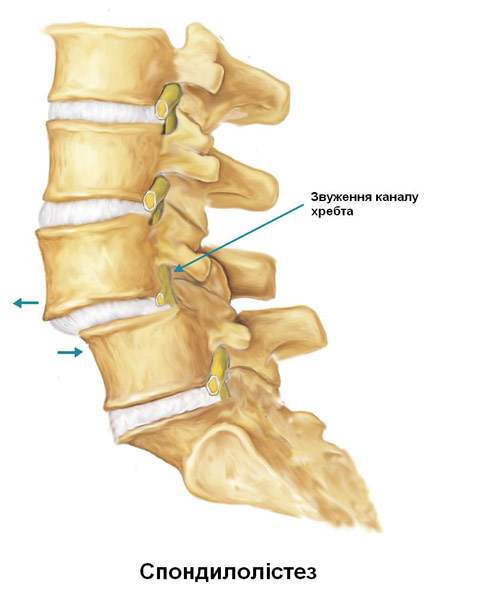

Спондилолістез - це захворювання хребта, при якому один з хребців зміщується вперед або назад по відношенню до інших хребців. Антеролістез - це зміщення хребця вперед, а ретролістез - це зміщення хребця назад по відношенню до іншого хребця. Спондилолістез може привести до деформації хребта, а також до звуження каналу хребта (стеноз центральної частини каналу хребта) або до здавлення корінців нервів, що виходять з міжхребцевих отворів (форамінальний стеноз).

Якщо пацієнт скаржиться на біль, оніміння, поколювання або слабкість в ногах, можуть бути проведені додаткові обстеження. Ці симптоми можуть бути викликані стенозом або звуженням міжхребцевих отворів, через які виходять корінці спинальних нервів. КТ або МРТ можуть допомогти виявити здавлювання нервів, викликане спондилолістезом. Це важливо для визначення варіантів лікування спондилолістезу, що буде описано нижче.